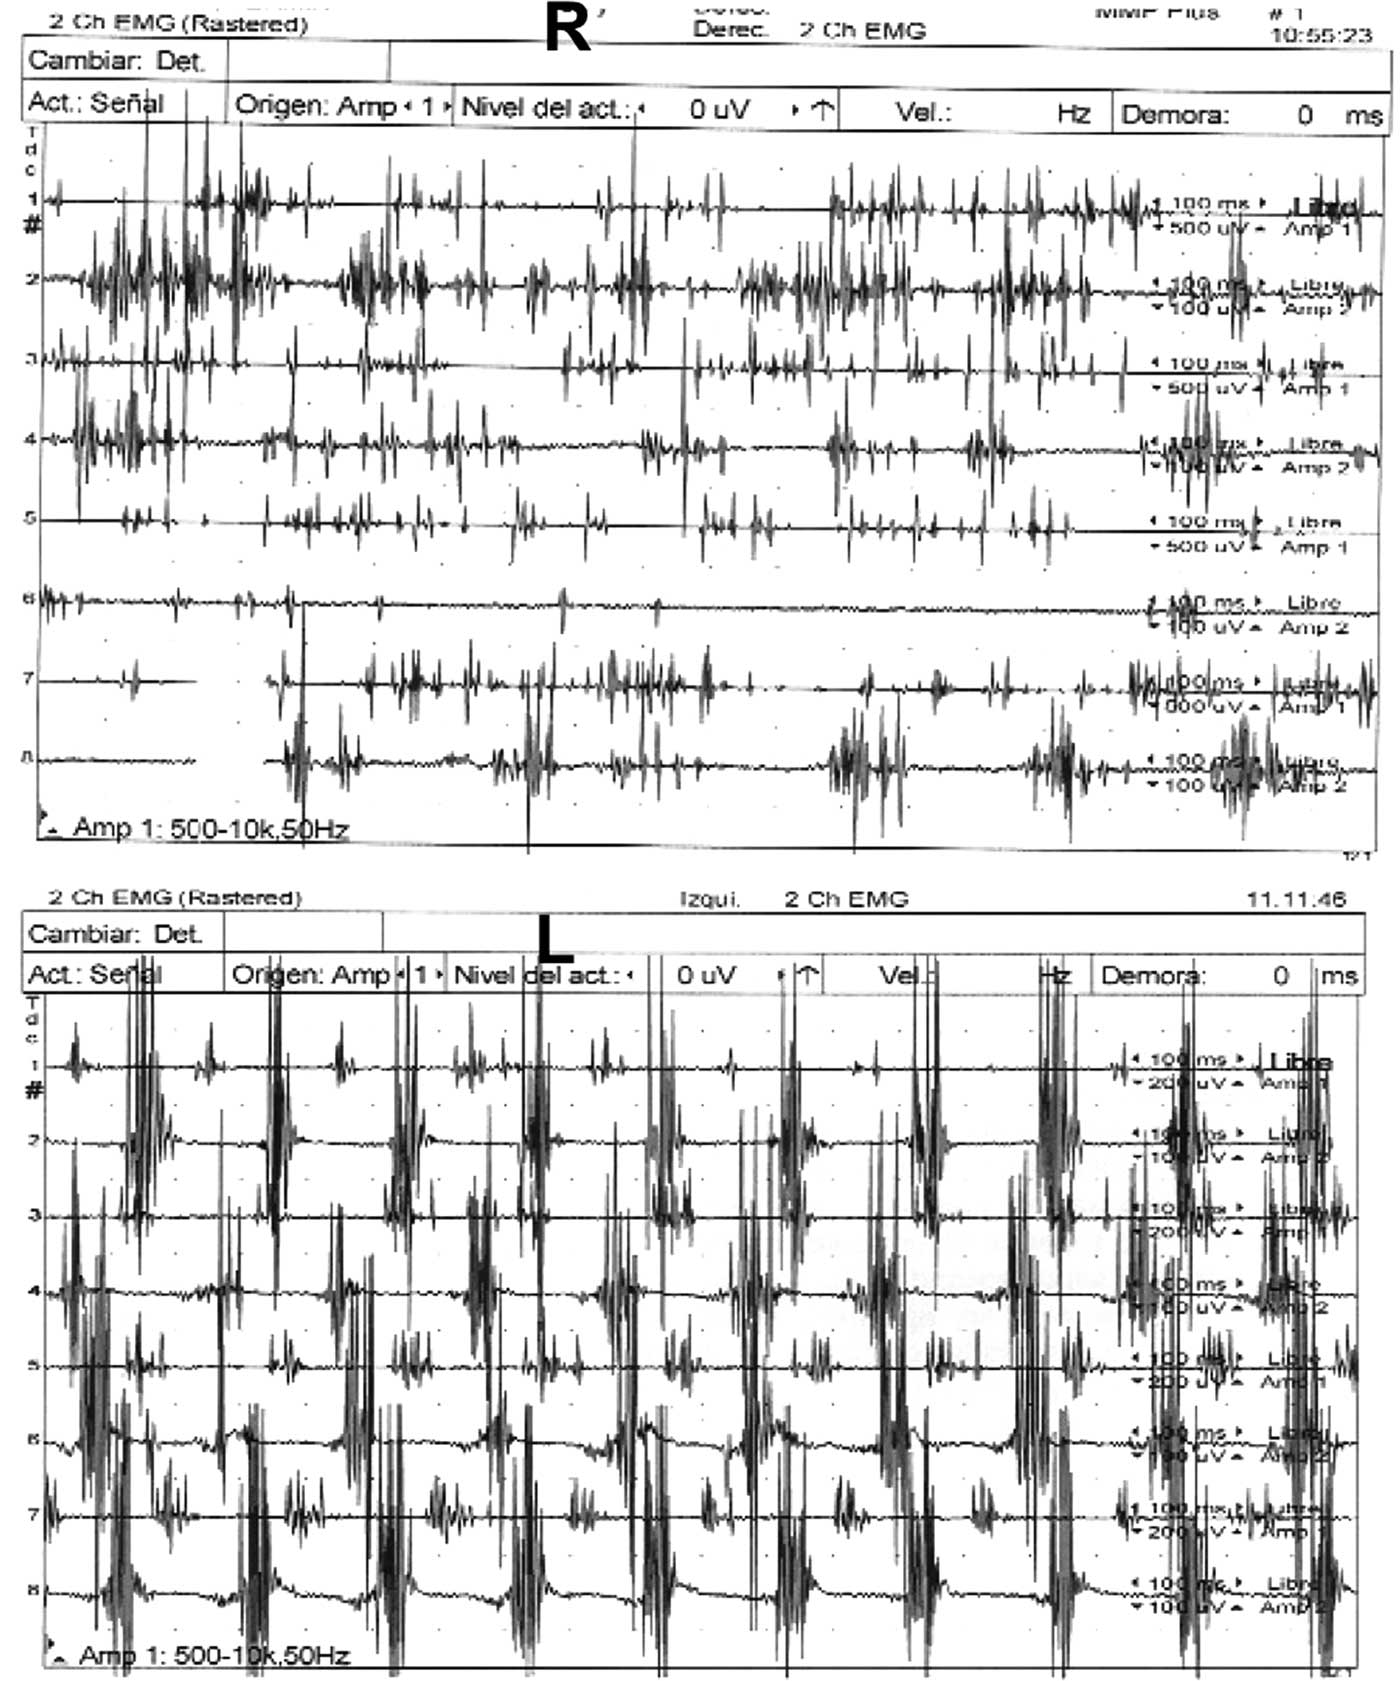

In 2014 clinical examination prior to beginning dopaminergic treatment demonstrated a bilateral tremor with inconsistent characteristics in his upper limbs: a coarse, irregular, low frequency resting tremor in the right arm which was accentuated by posture and further increased by goal-directed movements; on the left side, he had classic parkinsonian rest hand tremor without postural or intention tremor (video 1, segments 1-4). In addition, the patient had right homonymous hemianopia examined by confrontation, dystonic posturing in the right hand, mild hypomimia, chin tremor, and bilateral mild rigidity and bradykinesia (video 1, segment 5). Electromyographic recordings revealed alternating contraction of agonist and antagonist muscles of the left upper limb during the resting limb position at a frequency of less than 6 Hz and an irregular tremor at rest, at lower frequencies in the right arm (Figure 1). There was no co-contraction of the agonist-antagonist muscles in the right upper limb. Cranial MRI revealed left parieto-temporal atrophy with left ventricular ectasia, encephalomalacia in the left posterior cerebral artery territory, small infarction in the right cerebellum and lacunar infarction in the left thalamus (Figure 2 A-D). Single-photon emission computed tomography with I123 ioflupane (DaTSCAN) demonstrated a marked dopaminergic deficiency in the bilateral striatum (figure 3). PD was diagnosed and the patient received levodopa, reaching a final dose of 750 mg/day with positive response of the three components of HT. Rest tremor in the left arm, chin tremor and other parkinsonian symptoms (rigidity and bradykinesia) were slightly improved.

Figure 1 Electromyographic recordings of the tremor of both hands.